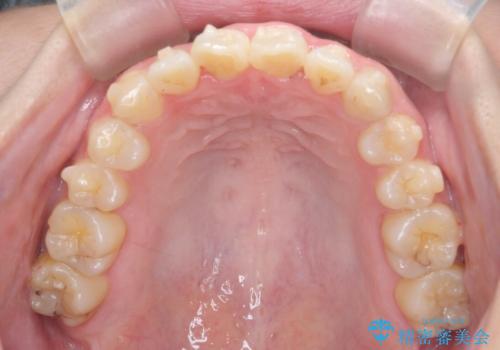

- 前歯のねじれを改善したい、と矯正治療を希望され来院されました。

上下の歯のがたつきを改善するマウスピース矯正治療と、下顎に見られる大きな骨隆起を外科的に除去する治療計画を進めていきます。

歯並びが改善したとともに、骨隆起を除去したことで舌をしまうスペースも増え安定した口腔内環境を確立することができました。